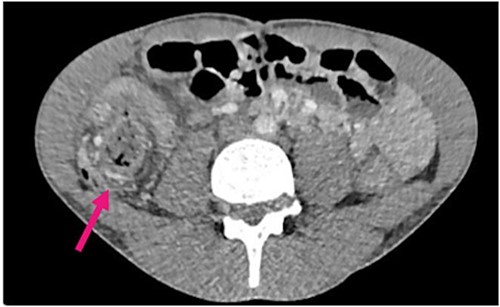

Radiological investigations included a contrast computerized-tomography (CT) of the abdomen/pelvis and suggestive of intussusception of the caecum into the ascending colon, with a thickened appendix. Due to the presence of faecal loading, it was not clear radiologically whether the combined clinical picture was suggestive of distal intestinal syndrome (Figs 1 and 2) due to faecal loading only, or true intussusception of the appendix.

Contrast CT axial sections showing the enhanced thickened appendix (white) intussuscepts with fat stranding, into the ascending colon. Distal faecal loading also observed.